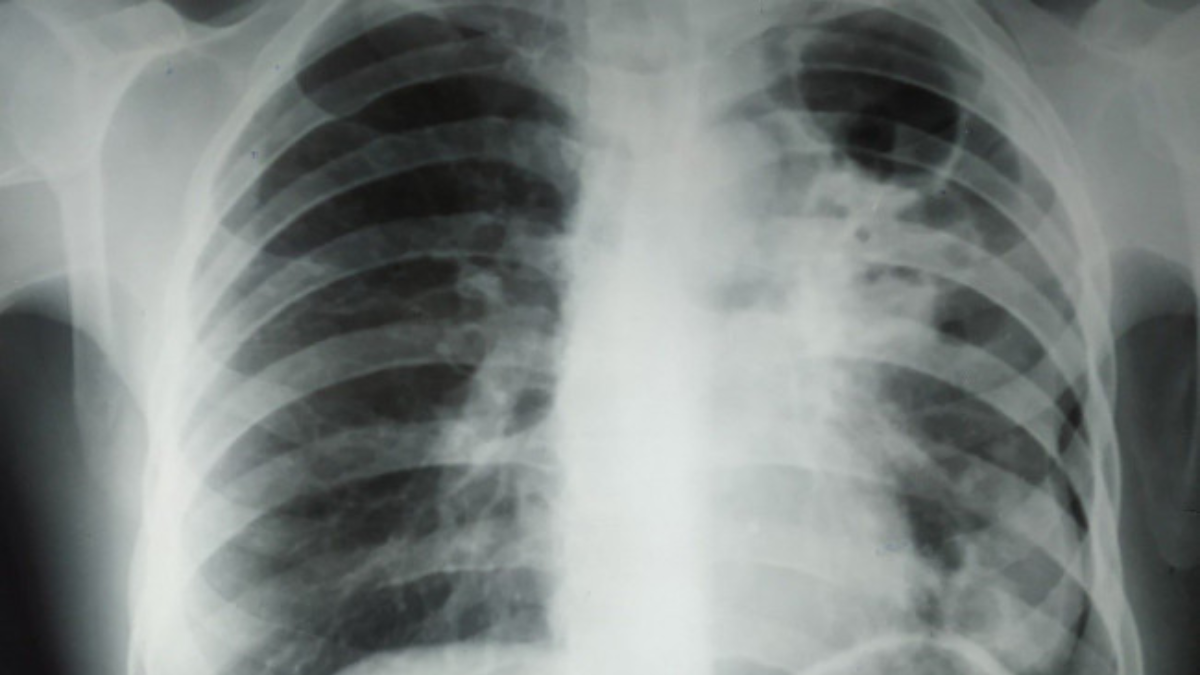

Фото: ілюстративне

Головне фото: ілюстративне